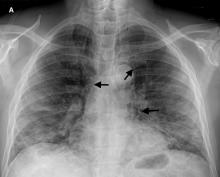

On hospital day five, the patient developed dysphonia, dysphagia, pleuritic pain, and subcutaneous emphysema in the supraclavicular region. His oxygen saturation was maintained at 97% with O2 at 3L / min through nasal cannula. A chest X-ray (Figure 1) and CT scan showed cervico-mediastinal emphysema (Figure 2) with pneumopericardium (Figure 3) and worsening lung infiltrates without pneumothorax.